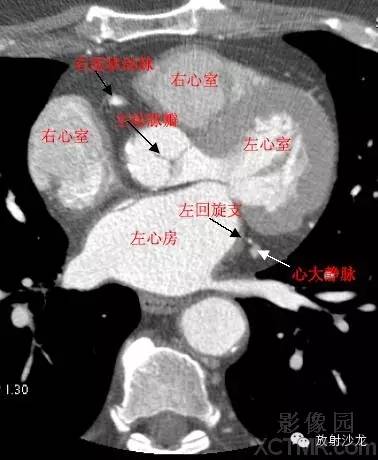

LA -Left Atrium左心房

RA -Right Atrium右心房

LV -Left Ventricle左心室

RV -Right Ventricle右心室

A.Aorta-Ascending Aorta升主动脉

LMA -Left Main Artery冠状动脉左主干

LCX -Left Circumflex Artery左回旋支

RCA -Right Coronary Artery 右冠状动脉

GCV–Great Cardiac Vein心大静脉